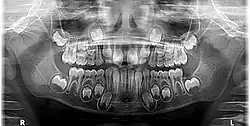

Differences between primary and permanent crowns

Primary teeth are the first set of teeth in the human dentition. It comprises 20 teeth, known as primary teeth or milk teeth. Primary teeth begin to erupt in infancy and are eventually replaced by permanent teeth. Premature loss of primary teeth can result in malocclusion or crowding of the permanent successors.[11]

Primary teeth differ from permanent teeth in several anatomical and structural ways. The crowns of primary teeth are generally shorter and broader, with a thinner layer of enamel, making them more susceptible to wear. This enamel also gives them a whiter appearance compared to permanent teeth.[11] In anterior teeth, mamelons, small bumps on the incisal edge of newly erupted permanent incisors, are absent in the primary dentition. The cervical ridges are more pronounced, particularly in molars, and the crowns are more bulbous with a distinct cervical constriction.[11]

Structurally, the roots of primary teeth are thinner and more widely spread, with short or absent root trunks. These adaptations facilitate natural exfoliation as the underlying permanent teeth erupt.[11]

Functionally and morphologically, primary molars have narrower occlusal tables and flatter buccal and lingual surfaces, whereas anterior primary teeth are proportionally wider mesiodistally compared to their crown height. These distinctions are important during dental assessments and restorative procedures.[12][13]